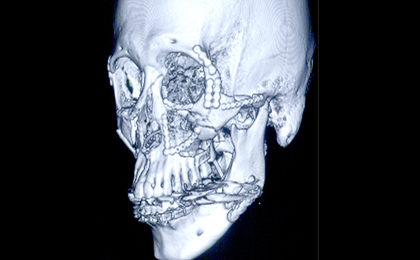

顔面のけがや顎の骨の骨折の治療を行います。

下顎骨の腫瘍で下顎を切除し(写真左)、切除したところを腰骨で再建し(写真中央)、インプラントを支えにしたブリッジ(写真右、白い部分)でかめるようにした症例のエックス線写真